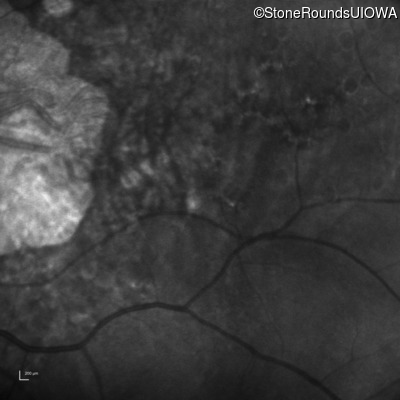

Infrared Fundus Photograph - Right - 10/200 sc

Exemplar

Infrared Fundus Photograph - Left - 10/200 sc